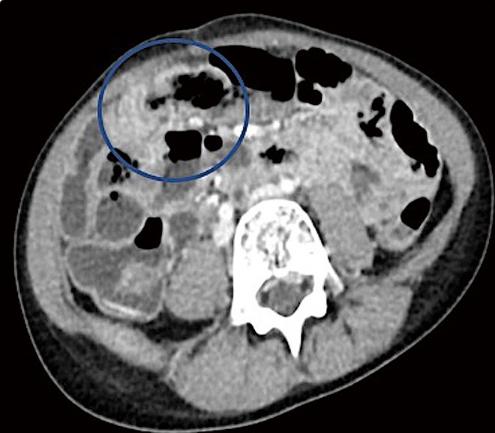

腹部和骨盆的CT与静脉造影显示多个突出的空气和充满液体的肠袢贯穿腹部。结果涉及回肠-回肠、回肠-结肠和结肠-结肠肠套叠累及远端横结肠/近端降结肠(图3、4、3、4)。在影像学证实的情况下,通过荧光剂对比灌肠对回肠-结肠肠套叠进行复位。插入一根儿童直肠管,通过重力将约360cc稀释的泛影葡胺直接注入结肠。本研究发现造影剂在整个结肠内自由流动,容易回流到回肠末端,表明在此手术之前成功减少或自发消退了轻微的回肠-结肠肠套叠 (图5)。

图4、轴向对比增强计算机断层扫描图像显示疑似结肠肠套叠(蓝圈)